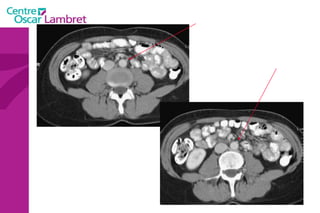

Il contient une partie minime du duodéno pancréas, l’intestin grêle, le colon. Le relief du colon et le mésentère (qui est le méso de l’intestin grêle) délimitent 5 compartiments : 2 gouttières pariéto-coliques droite et gauche entre colon droit et colon gauche et la paroi latérale de l’abdomen.  La gouttière droite communique : en cranial avec les loges inter-hépato-diaphragmatiques droite et sous-hépatique  en caudal avec le pelvis.                         Étage sous méso colique

2 loges dextro et sénestro-mésentériques, de part et d’autre du mésentère : Elles s’ouvrent en bas dans le pelvis.  Le dernier compartiment qui la partie la plus déclive est le cul de sac de Douglas : situé entre la rectum et la vessie chez l’homme (cul de sac recto vésical), entre le rectum et l’utérus chez la femme (cul de sac recto utérin). C’est le point le plus déclive de la cavité abdominale. Étage sous méso colique